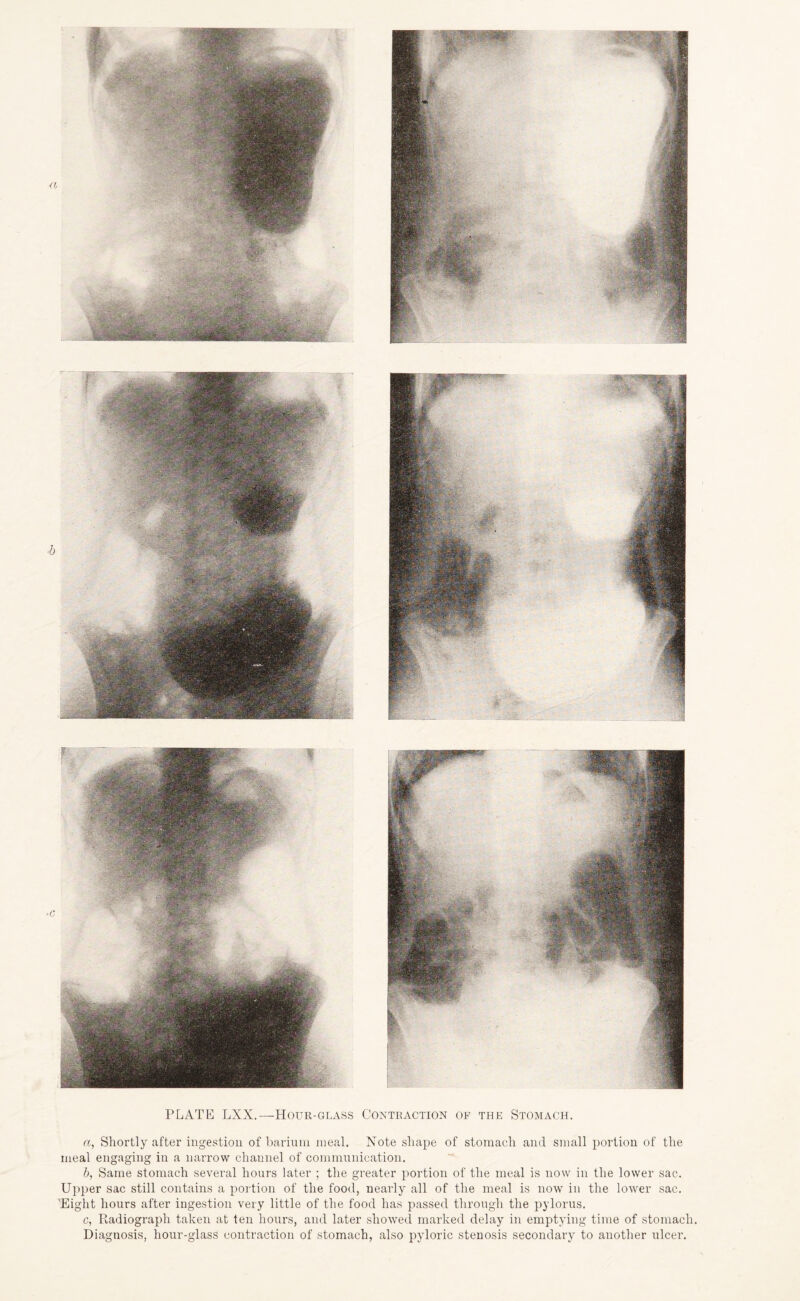

467/544 page 353